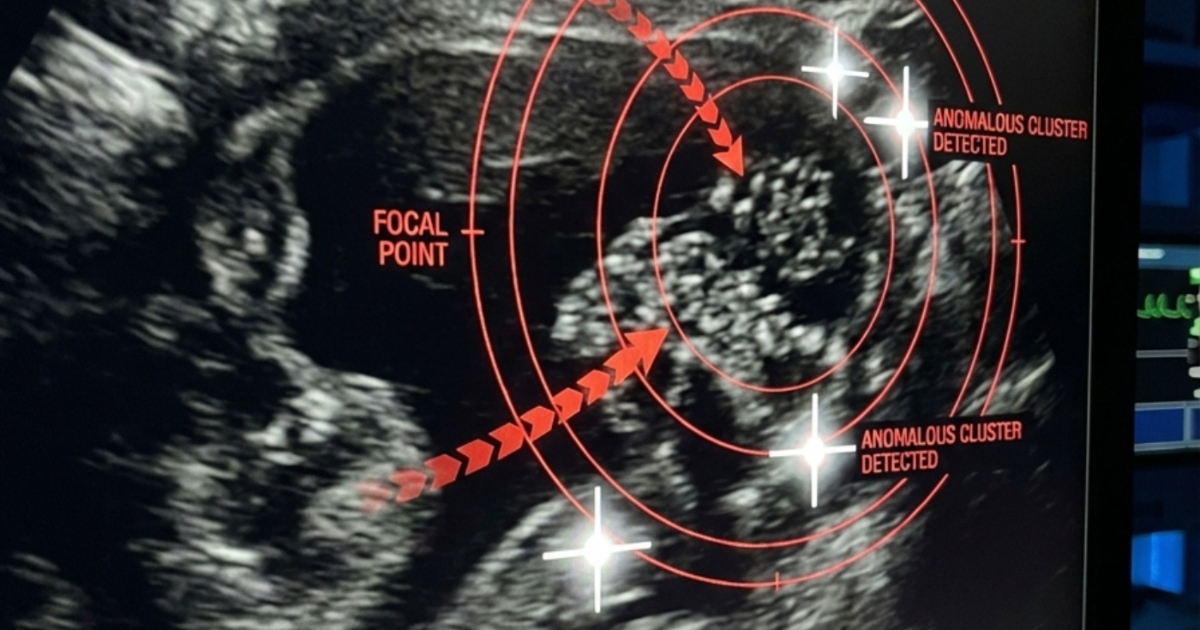

I akutmottagningens korridorer stannade tiden nästan. Min dotter vred sig av smärta på britsen medan vi under oroliga läkares blickar väntade på ultraljudsresultaten. Till slut kom doktorn fram och sa det varje förälder fruktar att höra:

Ryggvärken, som vi trott berodde på skolväskan, var i själva verket ett tyst växande njurstenproblem. Stenen hade lossnat och fastnat i urinledaren, vilket gav svåra smärtor och risk för livshotande komplikationer.